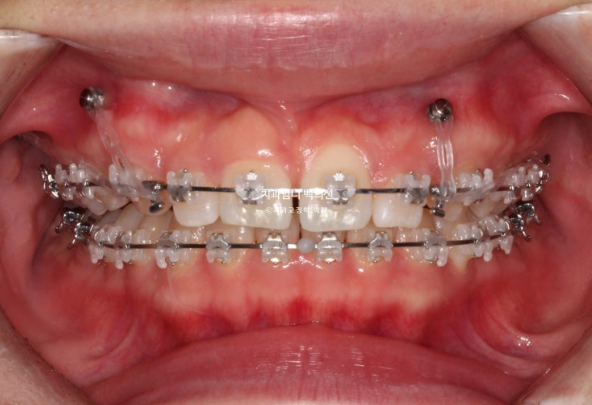

24.02

미니스크류를 사용했고

과개교합 해소를 위해 앞니에 바이트블럭도 붙였습니다.